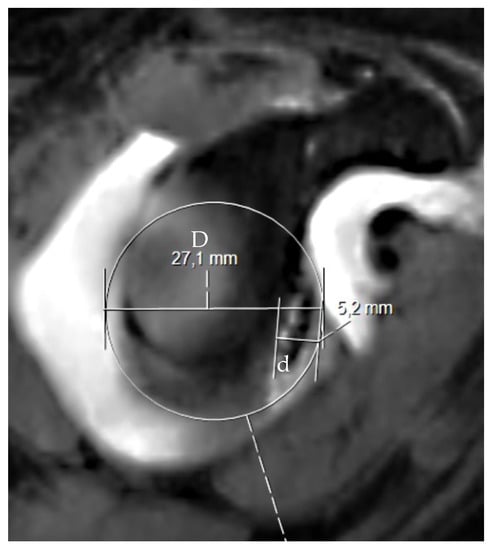

2. The Glenoid Track and Hill–Sachs Lesions: On-Track and Off-Track